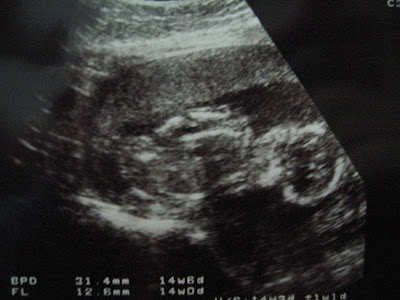

ultrasound scan

ni la antara ultrasound scan... yg latest tak smpt nk amik gambar... my camera rosak... :(

boy or girl pun tak tau lg... scan je... dia tak menunjukkan 'anu' nye.... nk buat 4D ultrasound scan... nanti upload resultnye : l